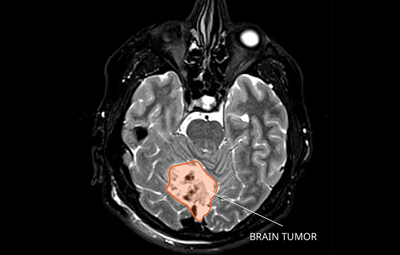

A Remarkable Recovery: How Teamwork and Advanced Treatment Helped a Young Boy Beat a Relapsed Brain Tumor

A 12-year-old boy who had bravely fought a type of brain tumor called medulloblastoma...